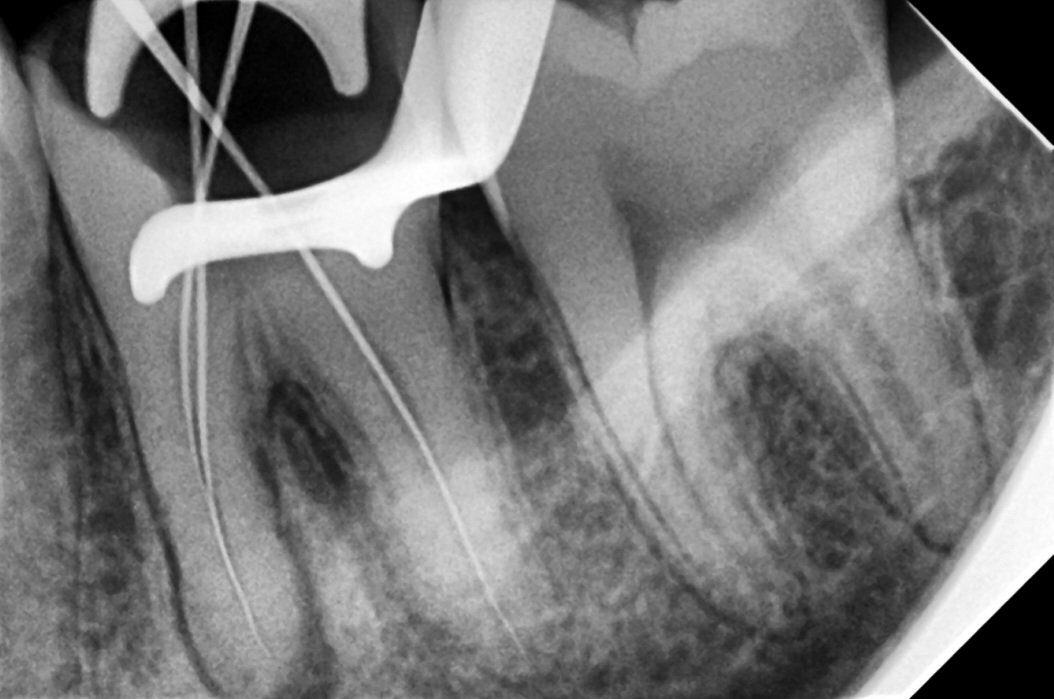

1. Diagnosis & Digital Imaging

Your tooth will be examined clinically and with digital X-rays to determine the extent of infection and the shape of the root canals.

A small opening is made in the crown of the tooth to access the infected pulp. The pulp is removed, and the root canals are carefully cleaned, shaped, and disinfected using modern rotary files.

• Use of digital X-rays, apex locators, and rotary systems for precision